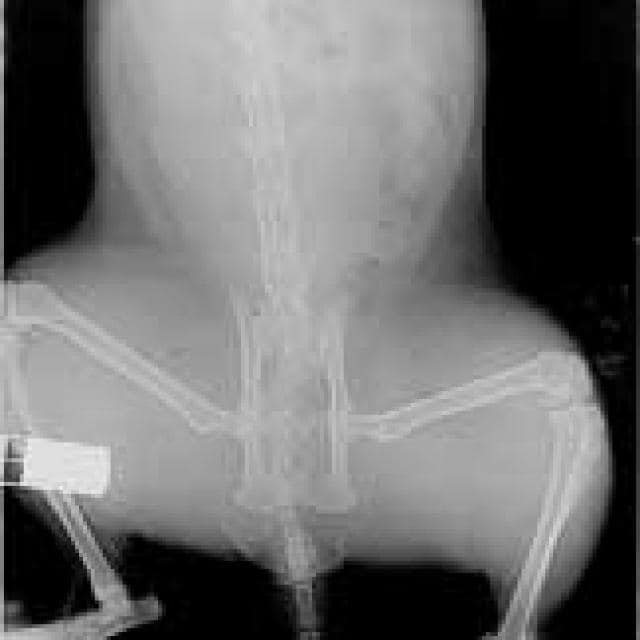

A veterinarian might suspect that a pet has a diaphragmatic hernia based on its history, clinical signs, hearing muffled lung and heart sounds through a stethoscope, and feeling a somewhat “empty” abdomen on palpation; but if the hernia is mild, the patient may appear to be normal. X-rays and sometimes an ultrasound are necessary to make a definitive diagnosis.

Serious hernias require surgical repair, and this is often no easy task. Many general practitioners will rightfully refer these cases to surgical specialists after the patient’s condition has stabilized. If the cost of surgery is prohibitive and the pet is minimally affected by the hernia, taking a wait and see approach is sometimes a viable option. Cats, in particular, are remarkably adaptable. In fact, I’ve diagnosed diaphragmatic hernias in cats years after the likely causative trauma occurred. I’m usually taking X-rays for a completely unrelated problem when I discover it.

Because diaphragmatic hernias can be so unobtrusive (and for other reasons as well), I always recommend chest X-rays when a pet comes in because of trauma, even if the patient looks perfectly normal. It’s always better to know that the hernia is there, even if you aren’t going to surgically repair it, than to be blindsided by problems down the road.